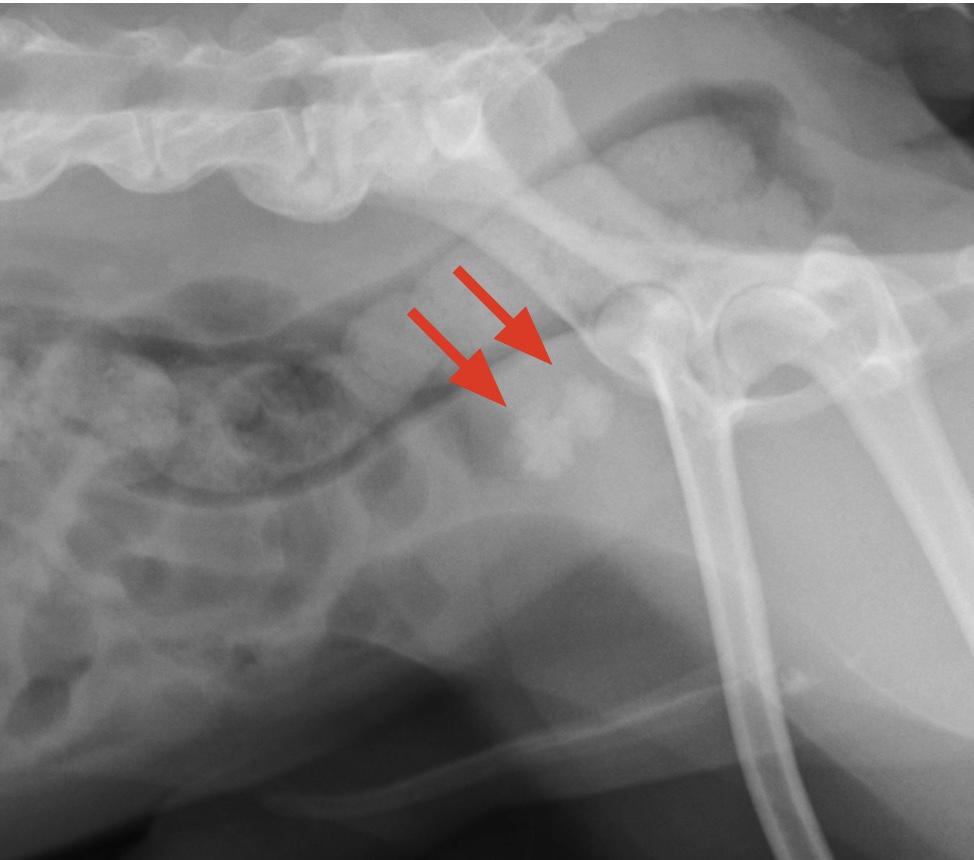

骨髄検査について

みなさん、こんにちは。院長の諏訪です。 先週から一気に冷え込み出しましたね。 急な気候の変化は人も動物も身体をこわしやすいものです。 注意してみてくださいね。 さて、本日は「骨髄検査」のお話をしようと思います。 What's 骨髄検査 ?? 骨髄検査と...